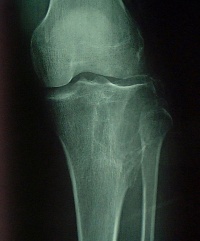

多见于年轻成人。肿瘤主要由巨细胞(破骨细胞)和基质细胞构成。骨巨细胞瘤在我国是较常见的原发性骨肿瘤之一,此瘤生长活跃,对骨质侵蚀破坏性大,如得不到及时妥善的治疗,可造成严重残废而导致截肢,少数病例尚可转移而致命。按良性和恶性程度分为三度。症状:邻近关节的肿瘤,生长缓慢,局部可有肿胀,疼痛及压痛,关节活动度常受限,瘤内出血或病理骨折往往伴有严重疼痛。检查:X线片表现:骨骺处有局限的囊性改变,一般呈溶骨性破坏,也可有“肥皂泡”样改变,其扩展一般为软骨所限。不破入关节,少有骨膜反应,肿瘤范围清楚,初发时病变在骨骺内旁侧,发展后可占骨端的全部,骨皮质膨胀变薄,有的可以穿破,进入软组织。X线片可显示其一般特点,但仍不足以确诊。

X线平片 对于骨巨细胞瘤的影像学检查, X 线平片是最具诊断价值的放射学检查手段。骨巨细胞瘤在X 线片上表现为骨端的溶骨性破坏,可侵及干骺端,向关节侧延伸侵及部分或全部邻近关节软骨下的骨皮

质。肿瘤大小与发生病变骨的大小有关。肿瘤延患肢骨长轴侵及的范围往往小于延横轴侵及的范围,在骨干侧可见筛孔样改变,而在骨端的周围可见明显的骨皮质膨胀、变薄。病变内部为不同程度的溶骨改变,皮质外多没有骨膜反应;当出现病理骨折时则可见骨膜反应。通常可见到骨膜下新生骨有中断,骨膜保持完整,病变的松质骨边缘部分可有明显的界限。骨巨细胞瘤没有肿瘤基质的矿物化,关节渗出少见,但经常伴有病理性骨折发生。长骨以外部位的骨巨细胞瘤在X 线片上无特征性表现,与其他溶骨病变没有区别。

X线主要表现为骨端变心位溶骨性破坏而无滑膜反应,病灶骨皮质膨胀变薄,呈肥皂泡样改变。

X线片表现:骨骺处有局限的囊性改变,一般呈溶骨性破坏,也可有“肥皂泡”样改变,其扩展一般为软骨所限。不破入关节,少有骨膜反应,肿瘤范围清楚,初发时病变在骨骺内旁侧,发展后可占骨端的全部,骨皮质膨胀变薄,有的可以穿破,进入软组织。X线片可显示其一般特点,但仍不足以确诊。